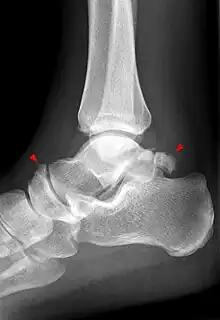

Talusul se vizualizează atât în incidența de față a gleznei[83] sau piciorului,[84] cât și pe cea de profil a gleznei sau piciorului, precum și în incidența oblică pentru articulația talo-calcaneeană.[83][85]

Pe radiografia de față a gleznei se identifică alături de talus și interlinia articulară a gleznei (tibio-fibulo-talară), iar pe cea de profil alături de talus (cu capul, colul și procesul posterior), spațiul articular talo-crural, articulația talo-naviculară,[83] precum și articulația talo-calcaneeană.[84] Tot pe radiografia de profil, se poate observa arhitectura regiunii, remarcându-se continuitatea traveelor osoase din tibie spre talus și calcaneu, iar de aici spre restul plantei.[84]